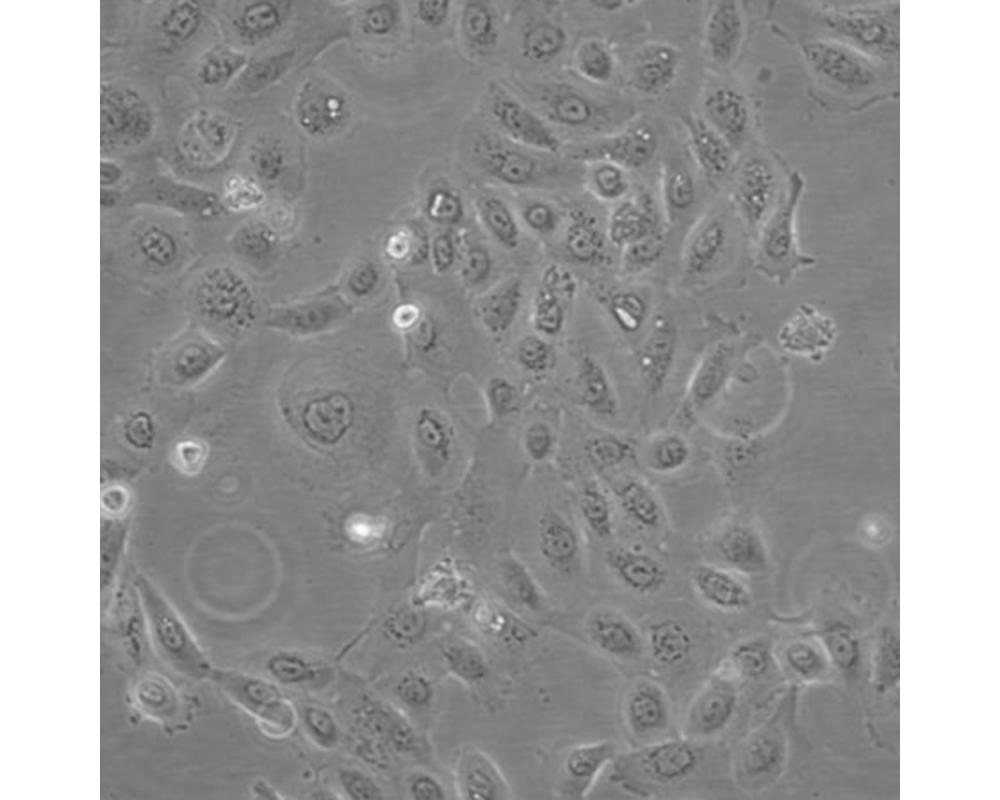

SCC-25

產品名稱 SCC-25

中文名稱 人舌鱗癌細胞

組織來源 舌鱗癌細胞;男性

生長特性 貼壁